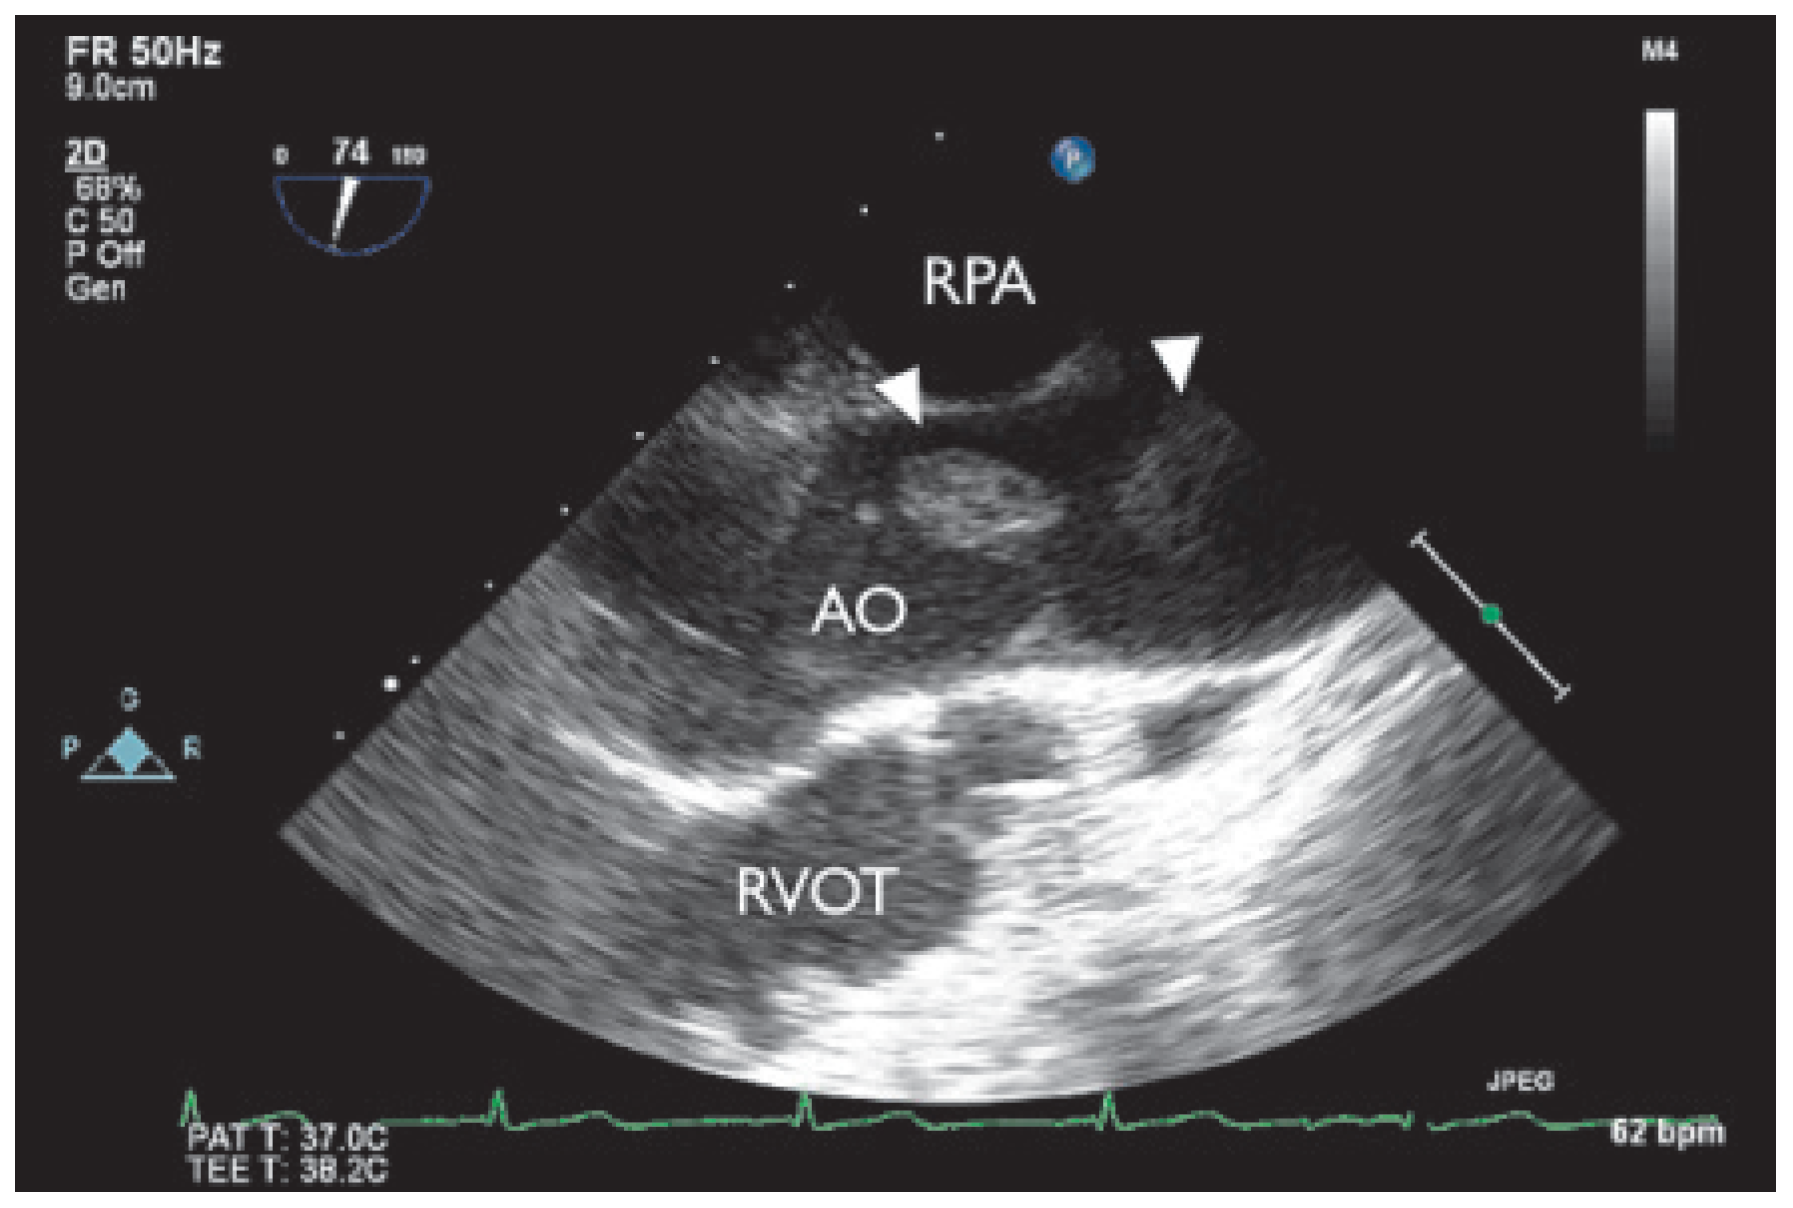

During the search for an embolic source, transthoracic echocardiography finally revealed three unusual structures in the ascending part of the aortic arch. The patient was further evaluated with transoesophageal echocardiography, which showed highly mobile structures within the ascending aorta (Figure 1 and Figure 2). One insertion site to the slightly thickened anterior aortic wall was detected approximately 4 cm distal to the aortic valve. Intracardiac thrombi could be excluded.

Figure 2. Multiplane transoesophageal echogardiography (74°), two thrombi with attachment to the anterior wall of the ascending aorta (long axis). AO = ascending aorta; RPA = right pulmonary artery; RVOT= right ventricular outflow tract.